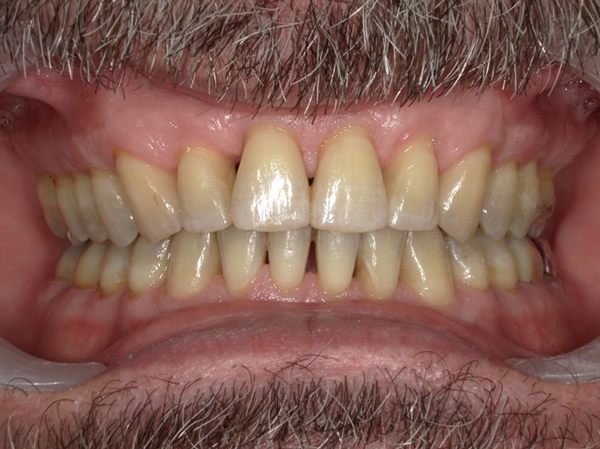

Présentation cas clinique :

Avant traitement

Après traitement